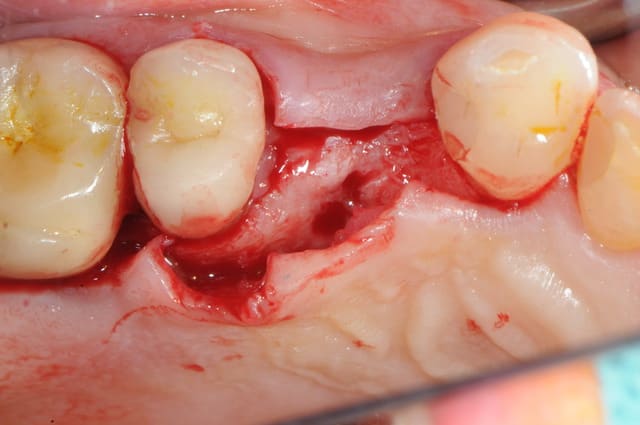

le cas que je vous présente date d'hier, il n'a rien d'extraordinaire, alors soyez indulgents, c'était juste pour le plaisir de partager ça avec vous.

ici, tu l'as compris, ce n'est pas vraiment nécessaire excepté pour la 2 ième prémolaire où l'extraction est très récente (2 mois à peine) et où l'alvéole à été comblée par un biomatériaux.